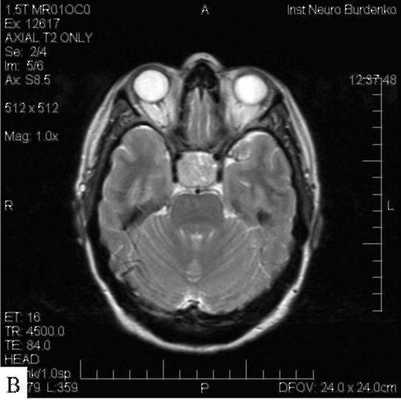

МРТ гипофиза при краниофарингиоме: сканы в разных проекциях

Магнитно-резонансная томография - один из высокоинформативных способов инструментальной диагностики. Исследование показывает мельчайшие изменения в структуре органов, предположительный характер патологии, взаимоотношение с близлежащими структурами. Скульптурирование многоплоскостных изображений во время МР-сканирования подразумевает использование принципа ядерно-магнитного резонанса, но не рентгеновских лучей. Атомы водорода в клетках воды, попав в поле, генерируемое аппаратом, начинают перестраиваться, при обретении привычного положения выделяется определенное количество энергии, которое фиксируют датчики, а обрабатывает компьютерная программа. Какого-либо вредоносного воздействия на организм во время диагностической процедуры нет, при условии отсутствия в теле металлических составляющих. Врач получает возможность рассматривать патологический очаг в любой плоскости, что невозможно при обычной рентгенографии или КТ.